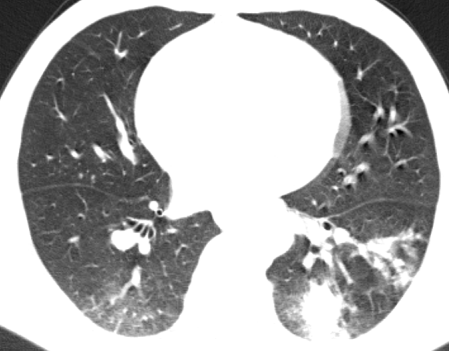

经过精心治疗,王某的症状完全消失。一个月后复查胸部 CT,结果显示较前明显吸收,这标志着王某的病情得到了有效控制,向着康复迈出了坚实的一步。信丰县中医院肺病科专家团队以卓越的医疗水平和高度的责任心,再次为患者带来了健康和希望,也赢得了广大患者的信任和赞誉。

治疗后CT影像▲